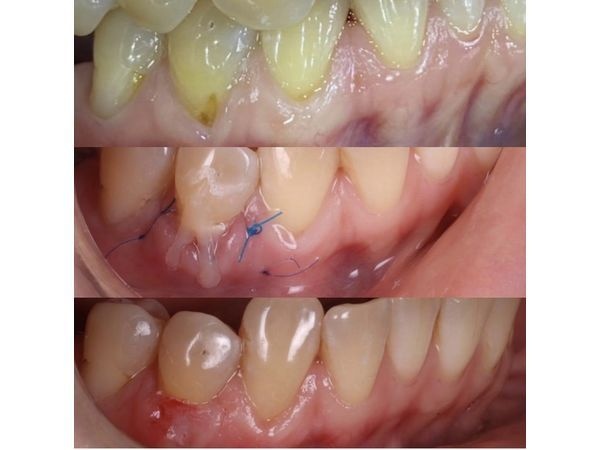

Замеры рецессии установили, что она принадлежит I классу по Миллеру: глубина — 3 мм (мелкая), не выходит за границы прикреплённой десны, биотип (толщина десны) средний, слизистых тяжей в области рецессии не было.

Пациенту провели туннельную пластику, в ходе которой сделали на десне надрез ниже области рецессии и поместили туда трансплантат, взятый из нёба. Место забора трансплантата ушили и тампонировали гемостатической губкой. На десну наложили швы, фиксирующие трансплантат, а также подвесной и композитный шов.

Боли после операции не было, но сохранялась незначительная отёчность. Швы сняли через 10 дней.